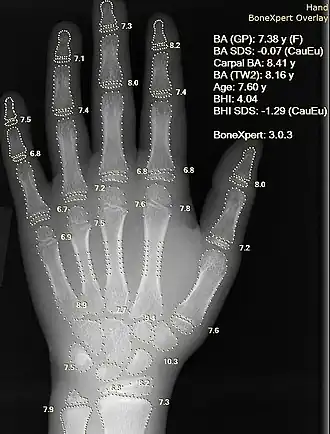

Since bone maturation is a good indicator of overall physical maturation, an X-ray of the left hand and wrist to assess bone age usually reveals whether the child has reached a stage of physical maturation at which puberty should be occurring.[2][7] X-ray displaying a bone age <11 years in girls or <13 years in boys (despite a higher chronological age) is most often consistent with constitutional delay of puberty.[7][37] An MRI of the brain should be considered if neurological symptoms are present in addition to delayed puberty, two findings suspicious for pituitary or hypothalamic tumors.[2][10] An MRI can also confirm the diagnosis of Kallmann syndrome due to the absence or abnormal development of the olfactory tract.[10] However, in the absence of clear neurological symptoms, an MRI may not be the most cost-effective option.[10] A pelvic ultrasound can detect anatomical abnormalities including undescended testes and Müllerian agenesis.[2][36]